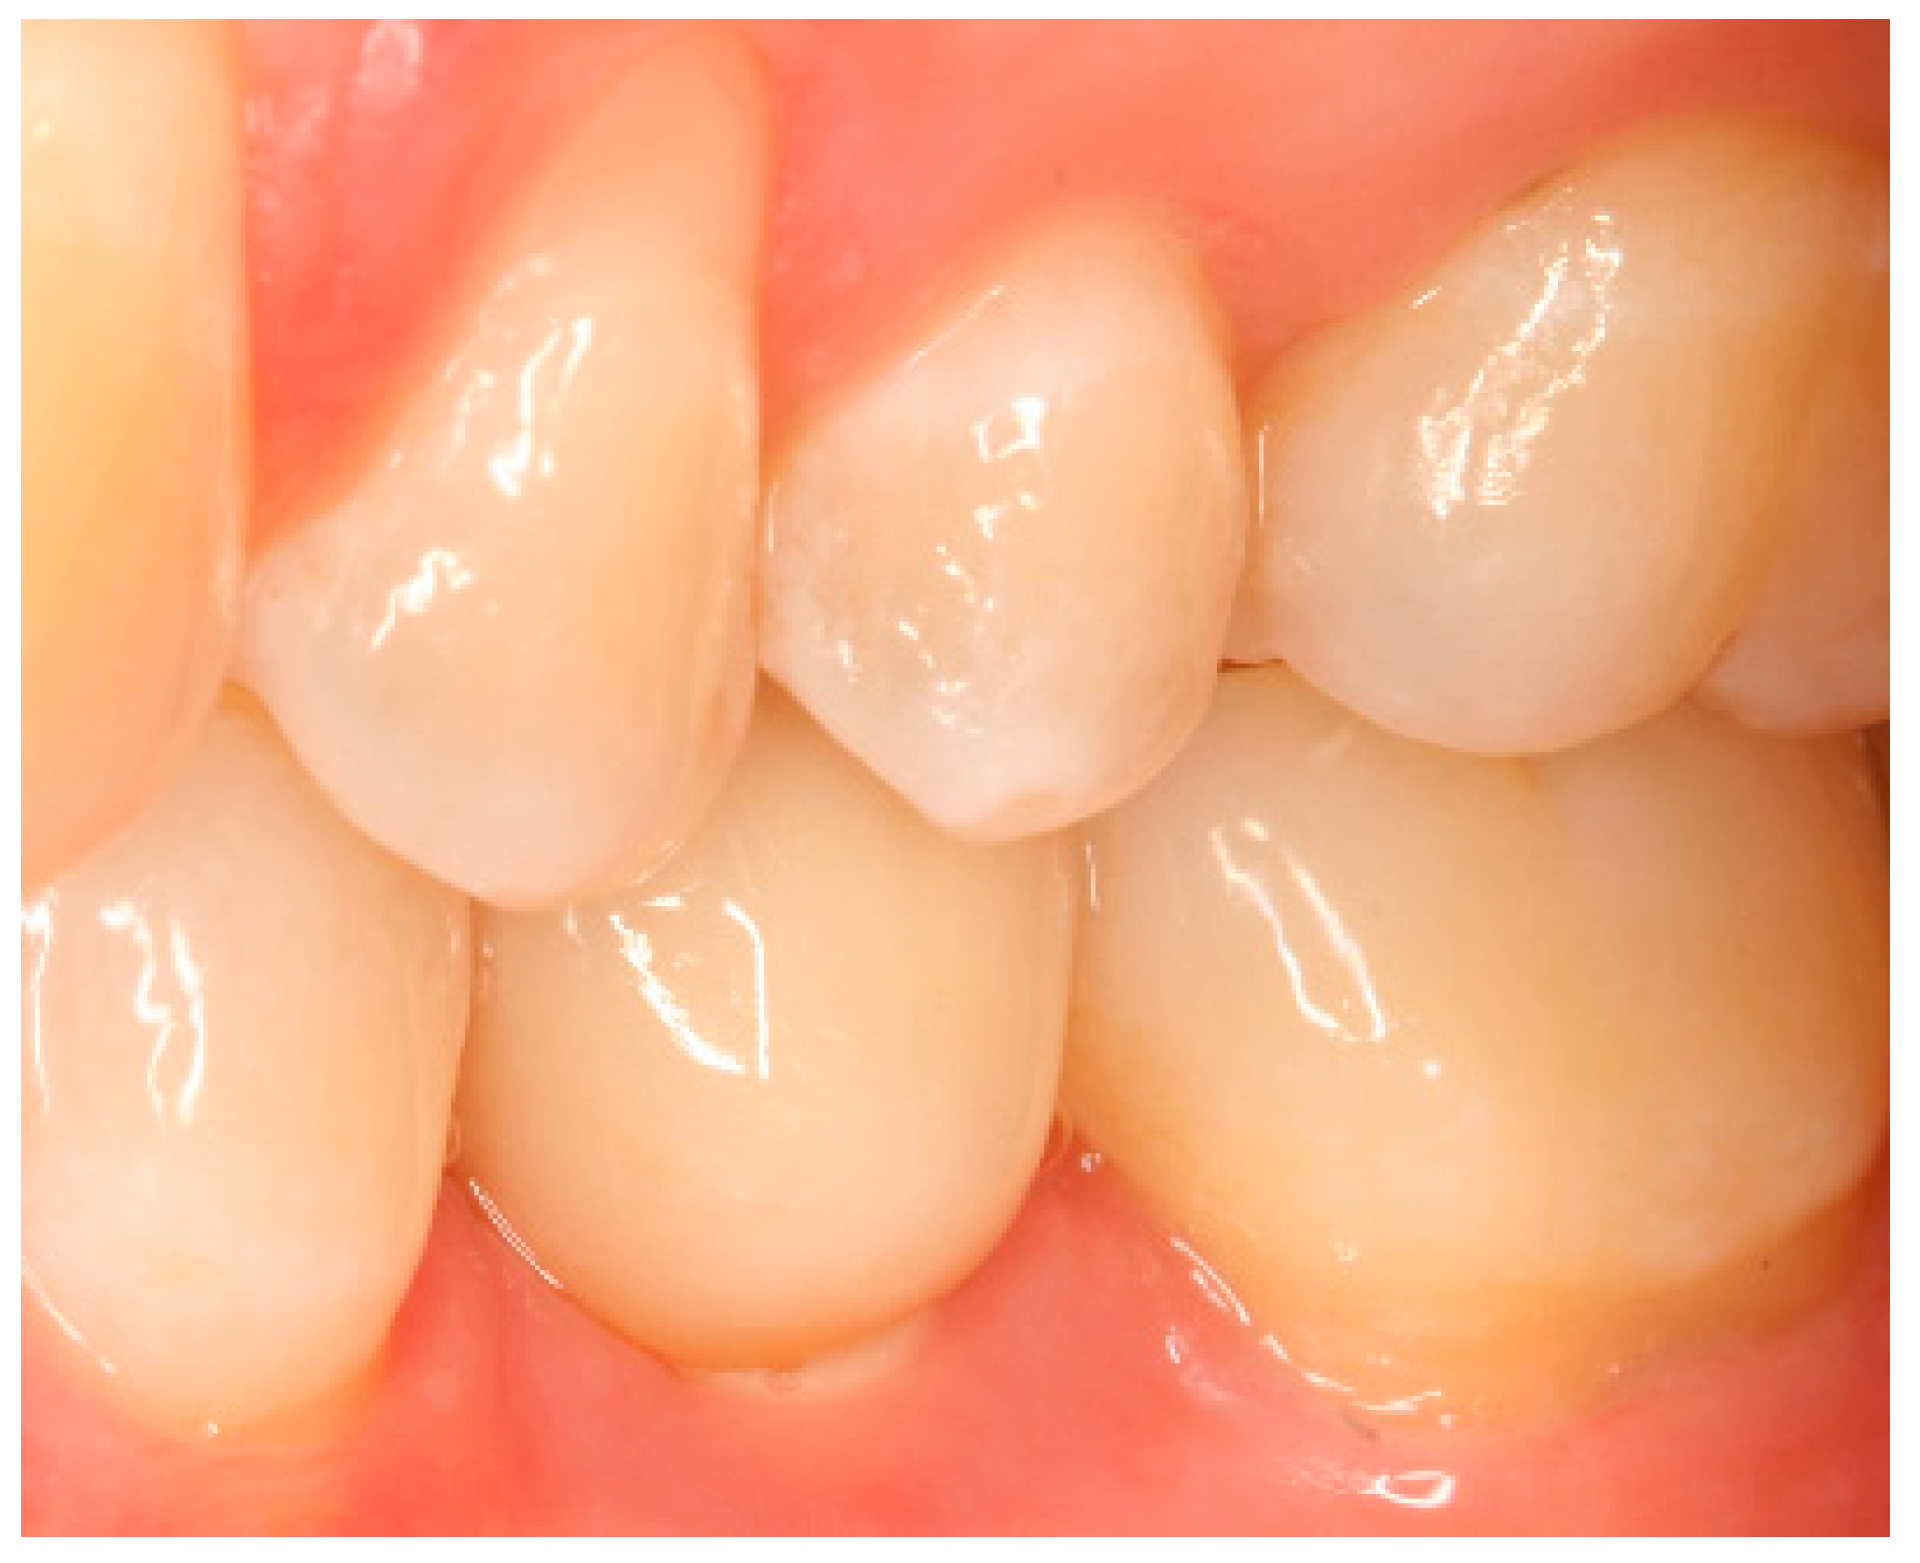

Situation after crown cementation. Lateral view.

Clinical situation at the 1-year follow-up. Lateral view.

Clinical situation at the 3-year follow-up. Lateral view.

Clinical situation at the 5-year follow-up. Lateral view.